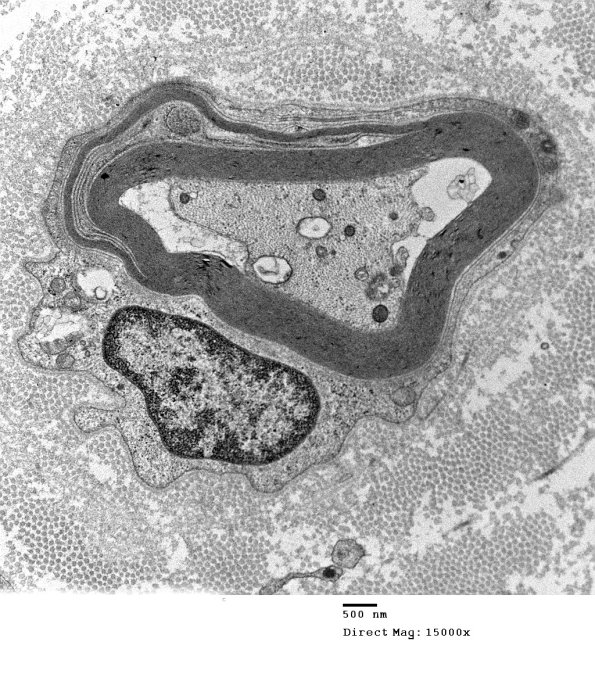

1E10A,B Although the outermost lamellae are preferentially involved, the pattern often varies. (electron micrographs)